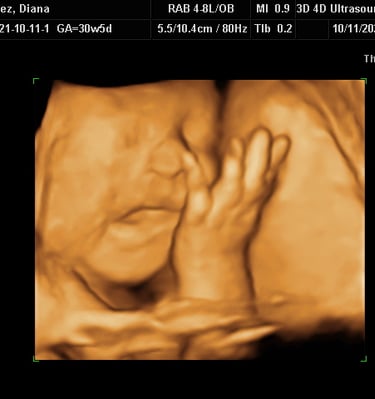

Our Gallery

Explore beautiful moments captured during our 3D and 4D sessions.